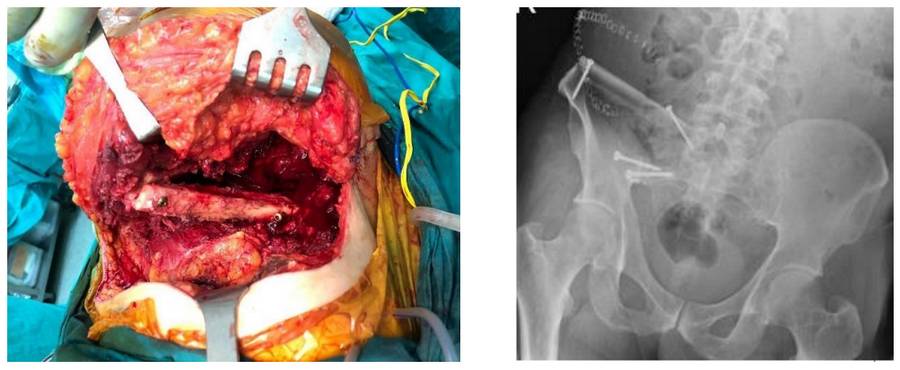

- After the tumorous portion of the bone was removed in one piece, a piece of fibula bone taken from the same leg was transferred to the resulting gap and secured with titanium screws.

Pre-operative examination: X-rays and CT scans show bone damage in the posterior part of the right pelvic bone and tumor tissue extending beyond the bone.

During and after the operation: The image shows the fibula bone being placed in between and secured with screws after the tumorous portion of the bone was removed.